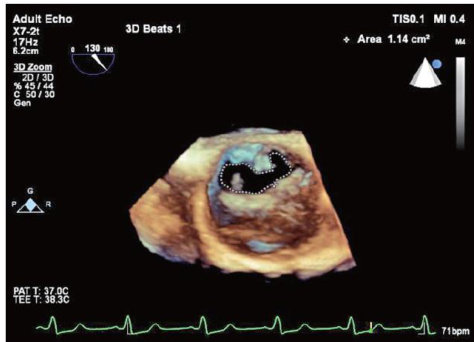

摘要 目的 探讨三维斑点追踪技术(3D-STI)评估主动脉瓣重度狭窄(AS)患者经导管主动脉瓣置换术(TAVR)后左心功能的临床价值。方法选取我院行TAVR的AS患者31例(AS组)和同期健康体检者31例(对照组),应用二维超声心动图获取左室舒张末内径(LVEDD)、收缩末内径(LVESD)、左室质量指数(LVMI),3D-STI获取左室整体主应变(GPS)整体纵向应变(GLS)整体圆周应变(GCS)整体径向应变(GRS)、三维射血分数(3D-LVEF),比较对照组与AS组,以及AS组术前与术后1、3、6个月上述参数的差异。结果与对照组比较,AS组术前LVEDD、LVESD、LVMI均升高,3D-LVEF、GPS、GLS、GCS、GRS均降低,差异均有统计学意义(均 P<0.001 ;AS组术后6个月LVMI仍升高,GPS、GLS、GCS仍降低,差异均有统计学意义(均 P<0.001 )。AS组术前、术后不同时间LVEDD、LVESD、LVMI、3D-LVEF、GPS、GLS、GRS、GCS比较差异均有统计学意义(均 P<0.05 )。与术前比较,AS组术后1个月LVEDD、LVMI均降低,GPS、GLS、GRS均升高,术后3个月和术后6个月LVEDD、LVESD及LVMI均降低,3D-LVEF、GPS、GLS、GRS及GCS均升高,差异均有统计学意义(均 P<0.001. );与术后1个月比较,术后3个月LVESDLVMI均降低,3D-LVEF、GPS、GLS、GCS均升高,术后6个月除LVEDD差异无统计学意义外,其余参数比较差异均有统计学意义(均 P<0.001 );与术后3个月比较,术后6个月LVMI进一步降低,GPS、GLS、GRS、GCS均进一步升高,差异均有统计学意义(均 P<0.001 )。结论AS患者TAVR后左心功能呈阶段性改善,3D-STI能早期、准确地评估其变化,具有一定的临床价值。